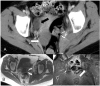

Amyloidosis comprises a rare spectrum of protein deposition diseases that diffusely or focally affect any organ. Amyloid's variable clinical presentation and nonspecific disease course often cause it to evade early diagnosis. This pictorial essay aims to familiarize radiologists with the pathophysiology of amyloidosis, to describe the basic classifications of amyloidosis, and to use multimodality imaging to illustrate its varied appearance throughout the body. This review highlights the diagnostic challenge of interpreting radiographic studies in patients with hematologic malignancies and concurrent amyloidosis. Radiologists should consider amyloid in chronically ill patients or patients with hematologic malignancies who have unusual/unexpected imaging findings.